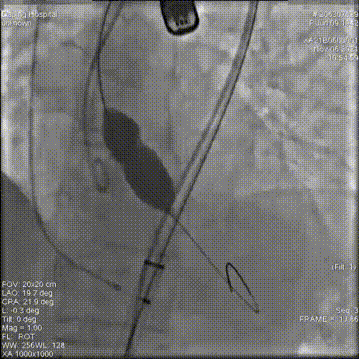

23mm瓣膜释放中

20mm球囊后扩前造影